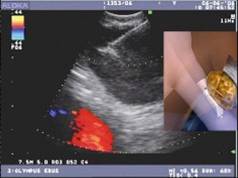

Ecobroncoscopia lineal (EBUS), técnica mínimamente invasiva de última generación

La Ecobroncoscopia lineal (EBUS, en siglas inglesas) es una técnica de última generación que combina la broncoscopia tradicional con la ecografía (el broncoscopio flexible presenta un transductor ecográfico convexo en su punta), de forma que permite ver directamente la tráquea, los bronquios y sus ramificaciones, y obtener imágenes ecográficas de las estructuras que se encuentran en contacto con la pared bronquial, especialmente ganglios linfáticos mediastínicos.